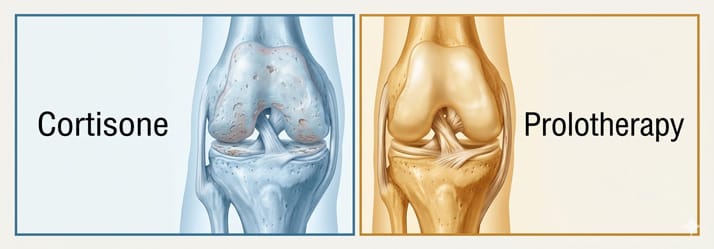

Prolotherapy for Knee Pain vs. Cortisone Shots: What Sarasota Patients Need to Know